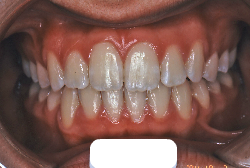

叢生(そうせい)

凸凹な歯並びのことを叢生といいます。矯正歯科に来院する患者様の主訴の中で、最も多いのが「配列の凸凹を真っ直ぐにしたい」というものです。歯の大きさと顎の大きさの調和がとれていないことが原因です。

凸凹を主体としたケースの場合、当院の平均治療期間は18ヶ月ですので、このケースは少し長めに経過しました。理由の一つは凸凹の程度がかなり重症だったと言うことですが、もう一つは、右下第2大臼歯が45度くらい前傾していたため、それを整直化させるために時間を要したと考えています。いずれにしても最終結果は大変よい状態と思います。

治療前は並びが乱れて見た目が悪いというのはもちろん問題ですが、歯科医学的に一番困るのは噛み合わせが悪いという点です。上下の犬歯(3番目の歯)は、上下的に離れた位置にあるため接触することができません。つまり歯としては存在していても、歯としては機能していないということです。